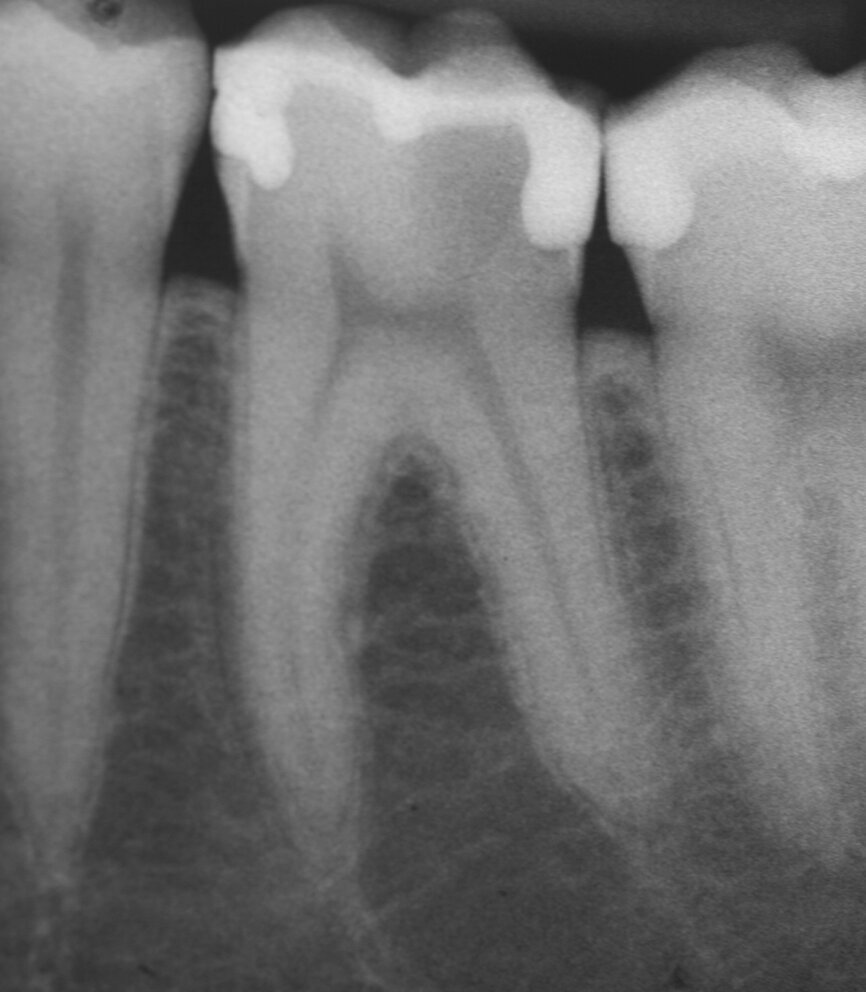

Apexification

In order to prevent extrusion of root canal filling material in immature teeth with open apices, MTA is used as an apical plug. The results of many studies have shown that MTA induced apical hard-tissue formation more often and its use was associated with less inflammation than with other test materials (Figs. 2a–g).[4]

Fig. 2a: (a) Endodontically treated tooth with fistula. (b) After retreatment, the tooth showed an open apex. (c) MTA application with the MAP System and PD MTA White. Condensation of the MTA with pluggers (d) or paper points (e). (f) MTA plug. (g) Post-op radiograph showing the MTA plug and the reconstruction with a fibre post.

Fig. 2b: (a) Endodontically treated tooth with fistula. (b) After retreatment, the tooth showed an open apex. (c) MTA application with the MAP System and PD MTA White. Condensation of the MTA with pluggers (d) or paper points (e). (f) MTA plug. (g) Post-op radiograph showing the MTA plug and the reconstruction with a fibre post.